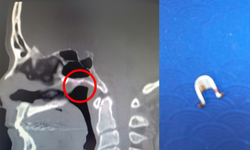

Cúc áo gãy đôi nằm trong đường thở bé gái 5 tuổi

Camera bệnh viện - 27/06/2025 19:24SKĐS - Bố mẹ đều đi làm, trẻ ở nhà chơi một mình nên không ai biết cháu đã nuốt phải dị vật từ lúc nào.